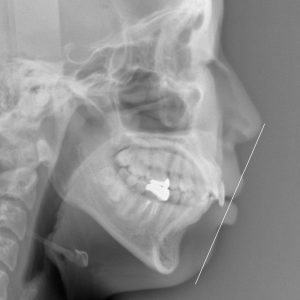

新着情報 979 治療前セファロ側面 – コピー Tweet 投稿日 : 2022年02月20日(日)カテゴリー : コメントを残す コメントをキャンセルメールアドレスが公開されることはありません。 * が付いている欄は必須項目ですコメント 名前 * メール * サイト 25歳 女性「 口もとを 下げたい 」( 上下顎前突症 ) ≫